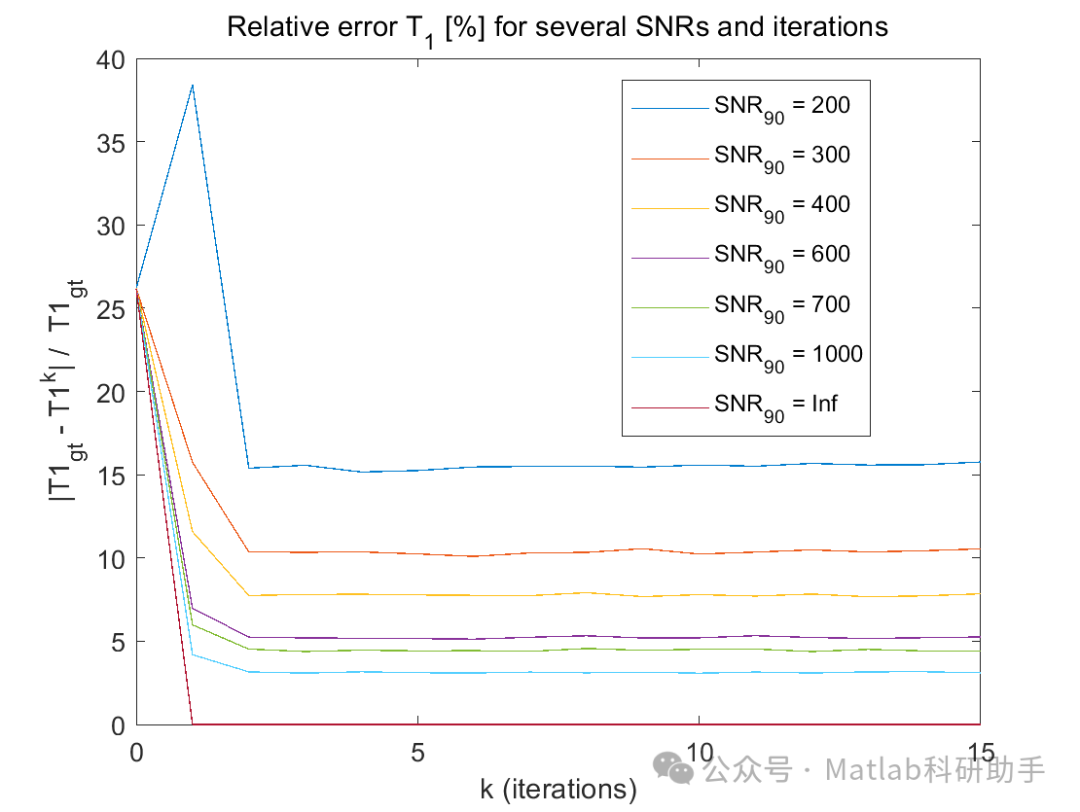

- 噪声敏感性:

在低信噪比区域,NLLS拟合的稳定性可能会受到影响。适当的图像去噪预处理或在拟合过程中引入正则化项可以提高算法的鲁棒性。

⛳️ 运行结果